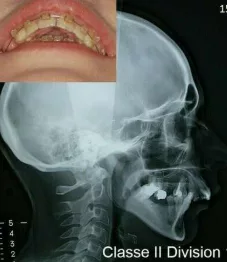

La mandibule est en retrait par rapport au maxillaire supérieur. Il peut s’agir d’un manque de développement de la mandibule et d’un maxillaire supérieur normal ou au contraire d’une mandibule normale et d’un maxillaire anormalement projeté vers l’avant. Parfois, les deux anomalies se conjurent associant un manque de développement de la mandibule et un maxillaire positionné trop en avant. Le profil facial classiquement observé est « convexe » ou « fuyant » tandis que l’on retrouve fréquemment une occlusion dentaire de classe II. L’appellation courante est le « rétrognathisme ».

Il existe de nombreuses variétés de Classe II squelettiques. Parmi les plus fréquentes, on distingue les Classe II squelettiques avec surplomb des incisives supérieures (Classes II Division 1) et les Classes II squelettiques avec recouvrement des incisives inférieures par les incisives supérieures (Classes II Division 2).

Classe II Squelettique Division 1 :

Classe II Squelettique Division 1